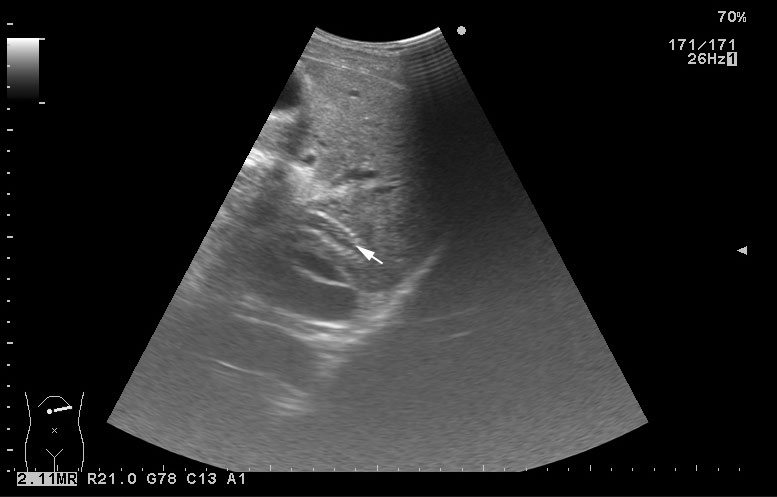

Молодой человек с циррозом печени и портальной гипертензией. Находился в стационаре в Испании, делалась какая-то манипуляция.

В печени обнаруживается какое-то инородное тело (стрелка)

TIPS, тромбоз: УЗИ

холедох стентировали?